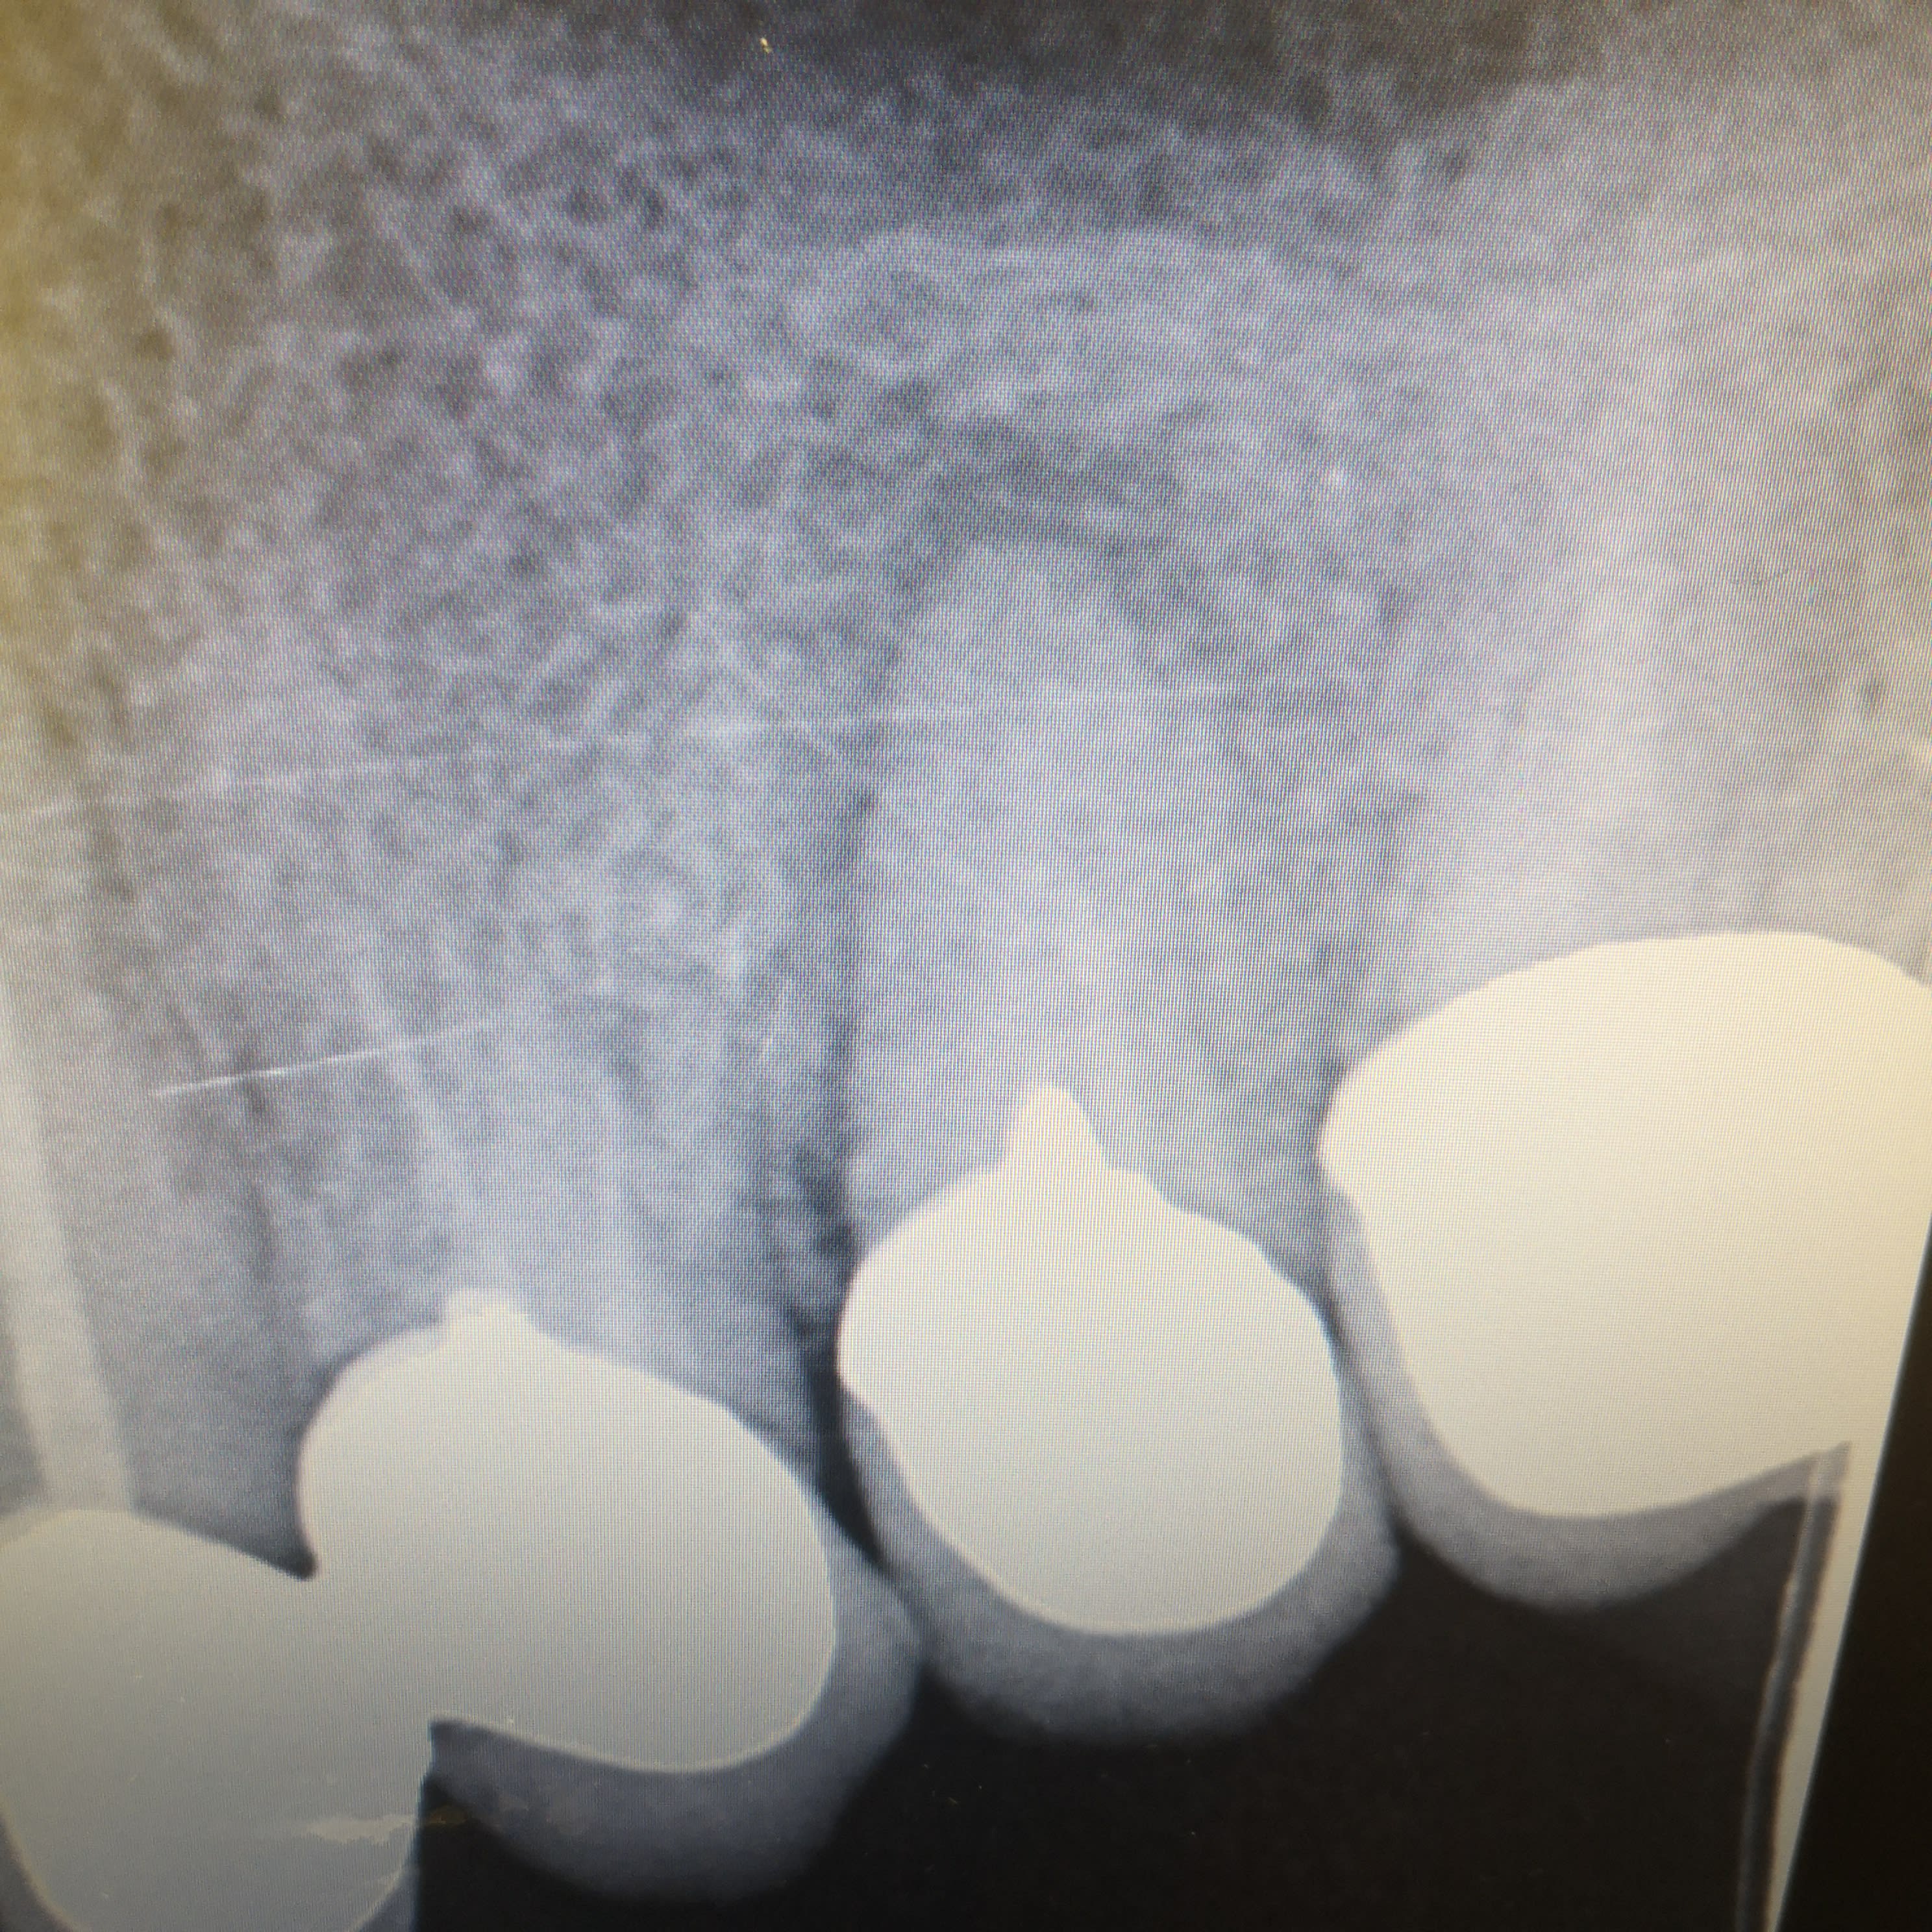

Et wouala ça y est je suis plus puceau de l'eri...

Extraction, curetage alvéole, laser sur l'apex et le periapex et remise en place en sous oc, calée au flow avec les voisines.

La 5

La radio était pas passée...